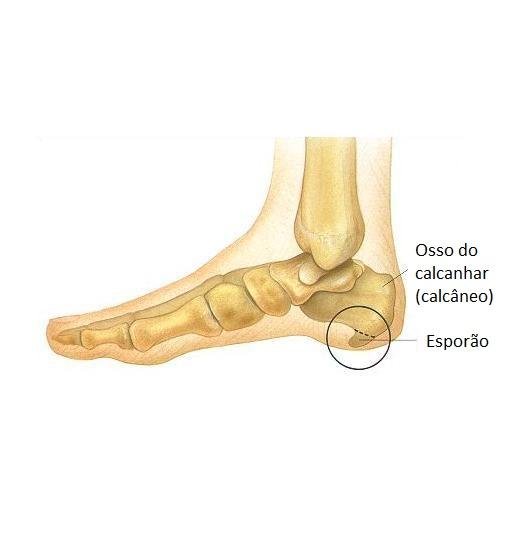

Um esporão calcâneo ocorre quando se gera uma formação óssea na zona inferior do osso do calcanhar, uma condição dolorosa e bastante incômoda que costuma ser resultado de uma fascite plantar não tratada. Devido a este quadro e aos incômodos que origina no paciente, a intervenção de um podólogo é fundamental para garantir uma adequada recuperação, um processo que pode ser longo. Curar ou tirar um esporão é trabalho de um podólogo, embora também existam alguns remédios naturais que o possam ajudar nisso. Enquanto não vai a um especialista, neste artigo do umCOMO explicamos-lhe como aliviar a dor de um esporão e melhorar seus movimentos.

A inflamação é a forma que o nosso corpo tem para proteger a zona sobrecarregada, o que se conhece como fascite plantar. Se esta condição não for cuidada e tratada, o corpo acabará por gerar uma calcificação na zona, ou seja, uma pequena formação óssea, o que causará dor e incômodos muito mais intensos e importantes, chegando inclusive a afetar a capacidade de caminhar distâncias médias e tendo impacto na realização de atividades cotidianas.